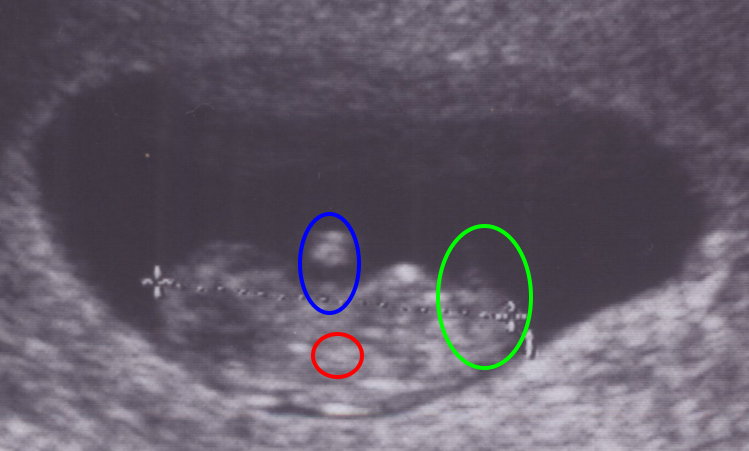

2007-05-26 大概是第十周 尺寸 - 2.87 cm

今天小小惡魔的奶奶來看寶寶了 小小惡魔也沒丟我們的臉 居然在醫生的指揮下 用力地揮動手腳 看到那一幕 我的眼淚快要飆出來!!!

crying 真的開始會動了耶... 不是只有心臟跳啊跳而已...... applause

紅色圈圈大約是心臟的位置 藍色圈圈是手手 綠色圈圈是屁屁+腳腳 小小惡魔就是這樣手腳揮動著和我們打招呼的喔!!!

第九周:從第9周開始已經可以稱為胎兒了,在醫學上才算是真正的小寶寶喔...

附加檔案 小小惡魔-20070526-身高-web.jpg (44769 bytes) (下載次數: 6094) (小小惡魔第一次用行動打招呼)